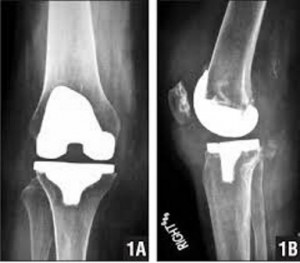

Η χειρουργική αντιμετώπιση περιλαμβάνει τον αρθροσκοπικό καθαρισμό της άρθρωσης, που μπορεί να καθυστερήσει την αρθροπλαστική για μερικά έτη, και εφαρμόζεται με τοπική αναισθησία , ανώδυνα χωρίς να χρειάζεται νοσηλεία στο νοσοκομείο (day surgery).. Η οριστική χειρουργική αντιμετώπιση της οστεοαρθρίτιδας του γόνατος γίνεται με την ολική αρθροπλαστική, κατά την οποία αφαιρούνται τμήματα της άρθρωσης που είναι κατεστραμμένα από την οστεοαρθρίτιδα και αντικαθίστανται με τεχνητή άρθρωση, φτιαγμένη από συνθετικό υλικό.